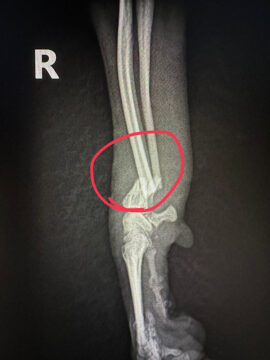

お願い 2024.09.01 2024.09.10 ブリーダー事件で保護されたプードルちゃんたちへご支援のお願い ▶︎ 続きはブログへ 毛呂山ブリーダー事件で保護されたトイプードル系の女の子3頭を、当会で迎えることになりました。 そのうち1頭は、レントゲン検査の結果、骨が完全に折れてしまっていることが判明し、後日、手術が必要な状態です。皆様からの手術費への温かいご支援を心よりお願い申し上げます。 受入れの様子について、続きはブログでご覧いただけます。 ブリーダー事件で保護されたプードルちゃんたちへご支援のお願い : ティアハイムさいたま公式ブログ 毛呂山ブリーダー事件で保護されたトイプードル系の女の子3頭を、当会で迎えることになりました。前回に引き続き、このような子たちがまだたくさんいることに、私たちも心を痛めています。 前回の受け入れ報告ブログ 動物指導センターから引き渡された子たちは、想像を絶す 毛呂山ブリーダー事件で保護されたトイプードル系の女の子3頭を、当会で迎えることになりました。前回に引き続き、このような子たちがまだたくさんいることに、私たちも心を痛めています。 前回の受け入れ報告ブログ 動物指導センターから引き渡された子たちは、想像を絶す Post マルプーの子犬譲渡会、大盛況で終了いたしました 前の記事 パテラ(膝蓋骨脱臼)グレード3の手術を終えました 次の記事